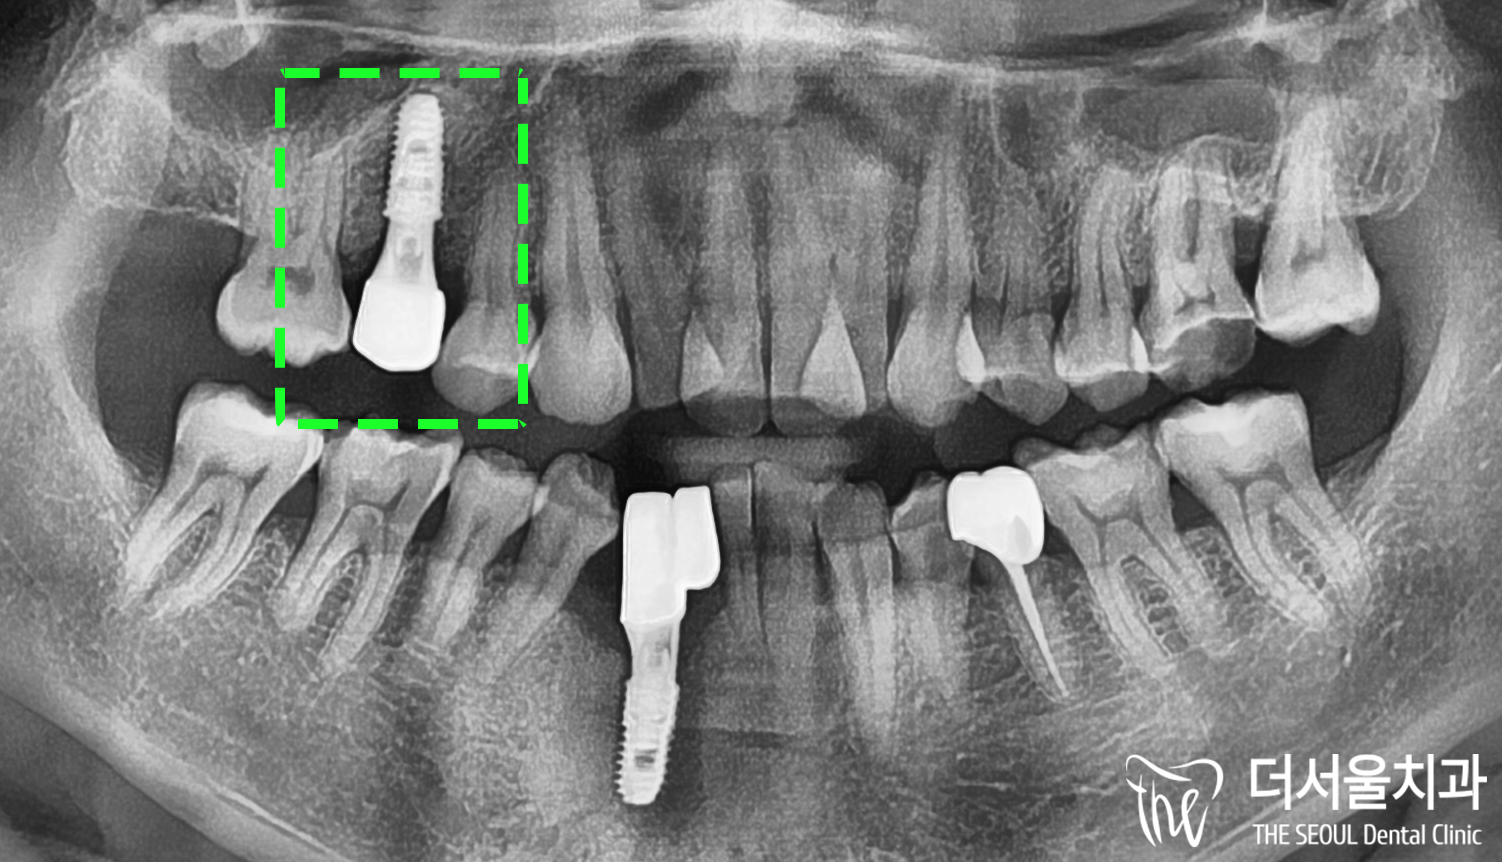

이렇게 임플란트 수술은 완료되었습니다.

옆에 있는 치아와 비슷하게 만들었으며,

아랫니와 교합이 잘 이뤄질 수 있도록

꼼꼼히 만들었습니다.

엑스레이로 체크했을 때도

식립하려는 위치에 잘 심어졌네요.

뼈이식 또한 결과가 좋구요. ^^